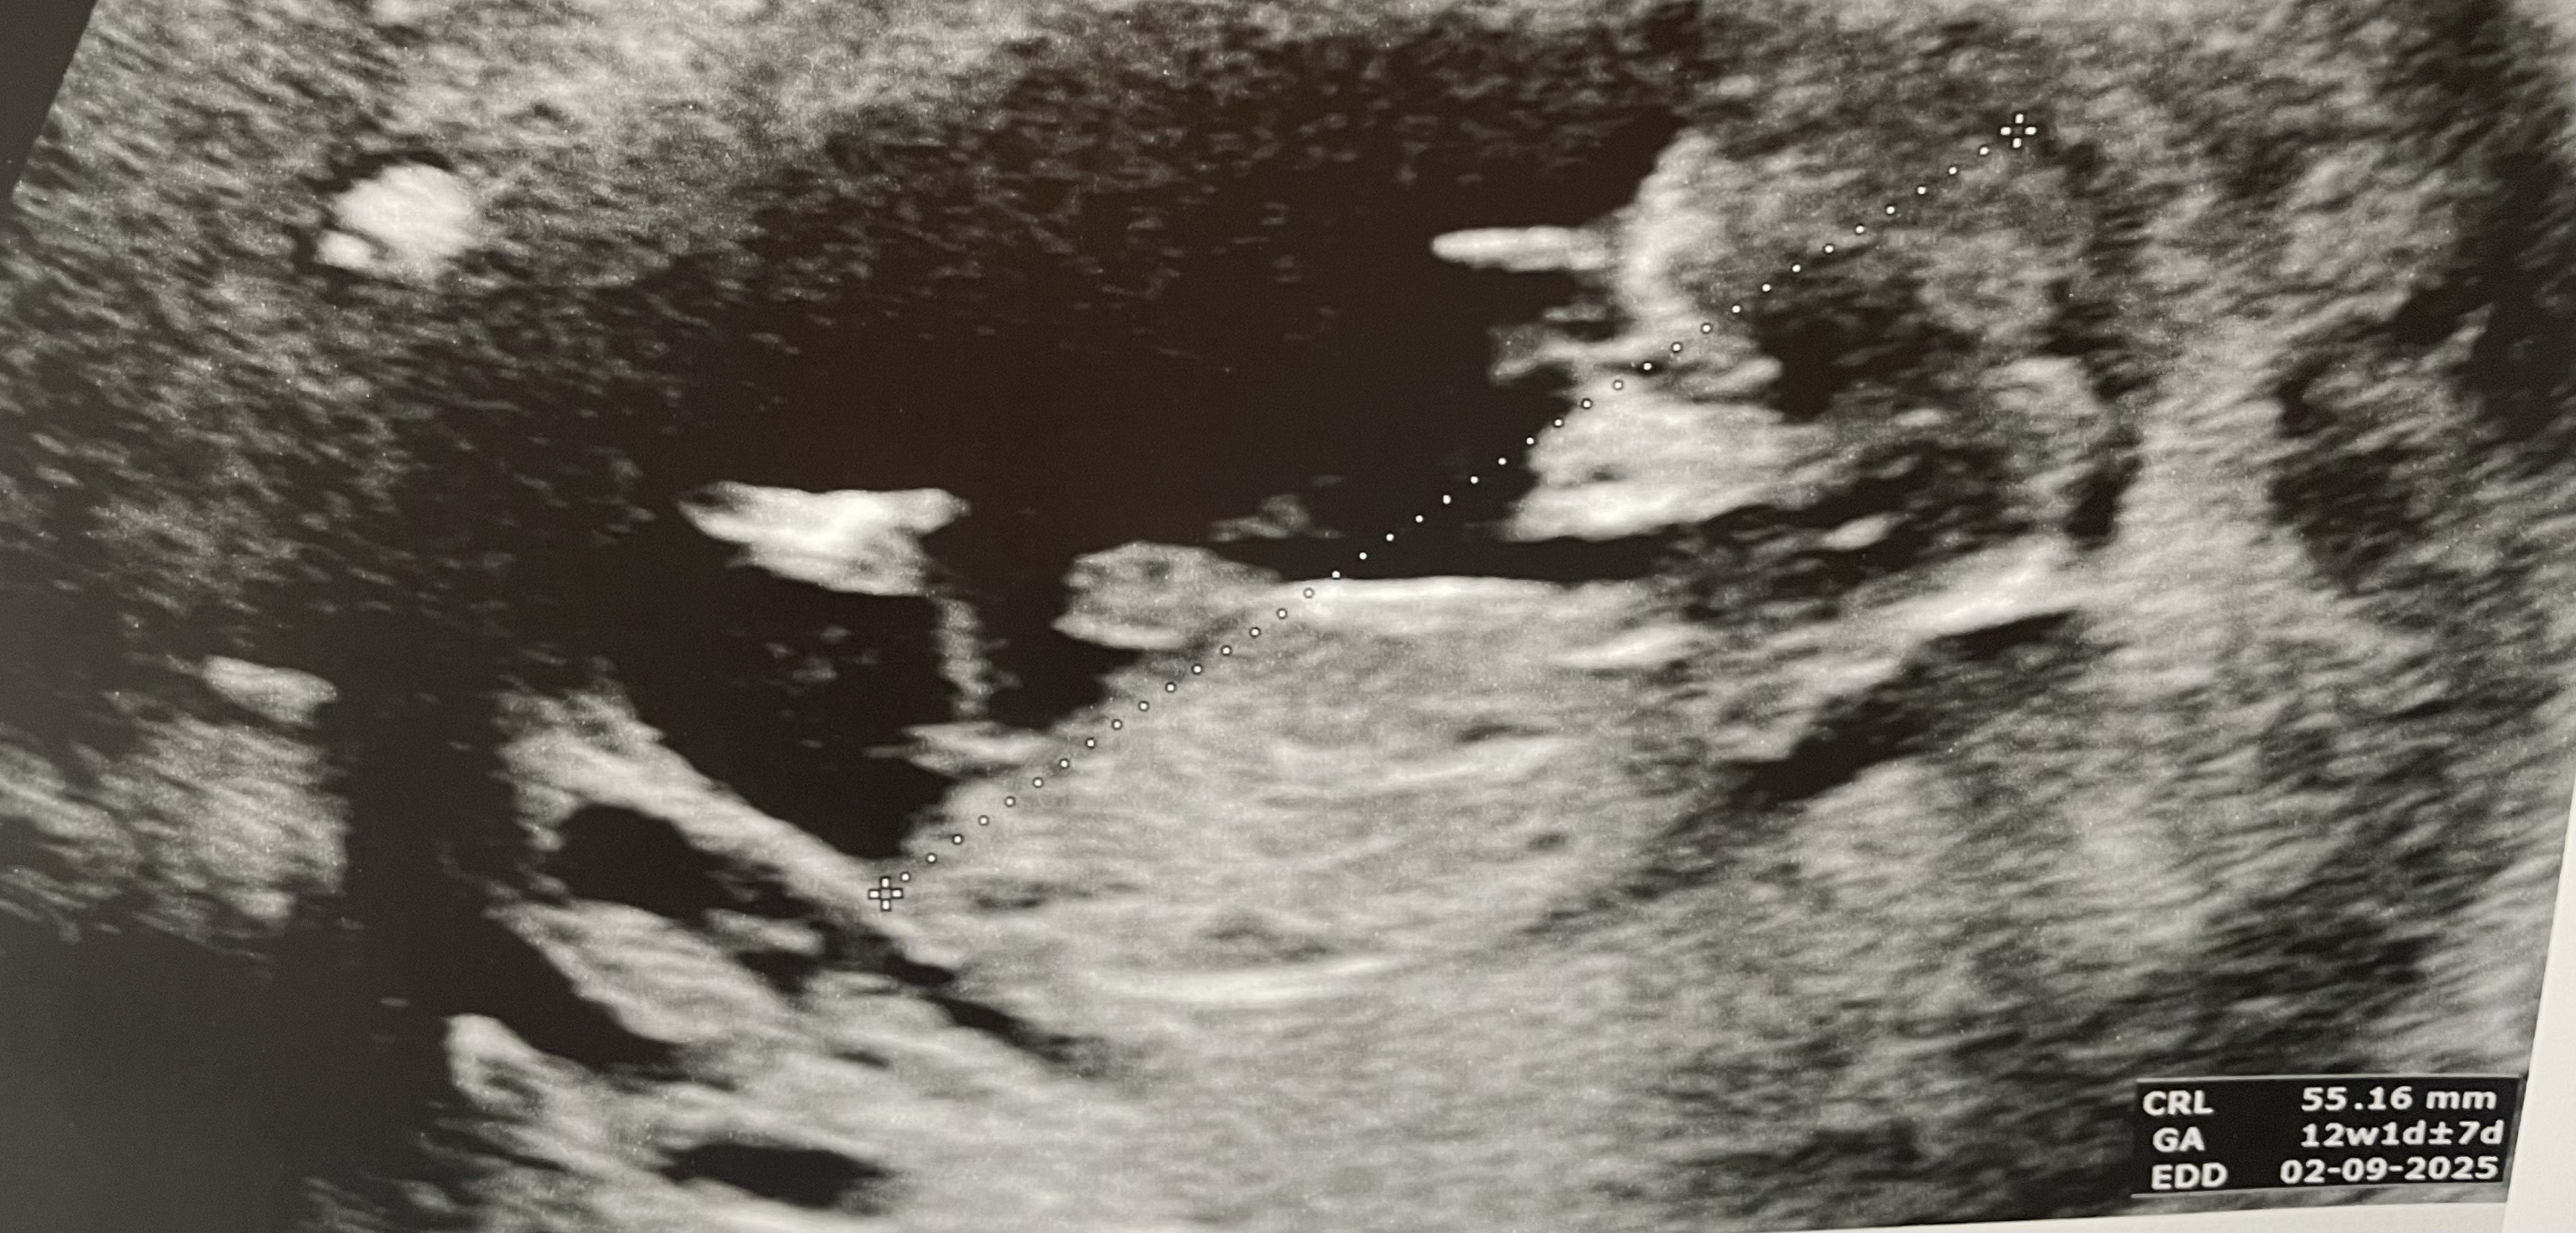

Näkyisköhän tässä?Ei näy mun silmään.![]()

Näkyy!!!!!!! Tosi tyttömäinen, mutta vielä on pieni mahdollisuus nousta pojaksi. Jos haluat tai sulla on face niin kannattaa kysyä nubtheoryqueens ryhmästä. Siellä on kätilöitä arvioimassa ja osuvat tosi usein oikeaan. Mä en aina huomaa semmoista pieniä merkkejä mitä ammattilaiset huomaa.Näkyisköhän tässä?![]()

Ok kiitos sulle! Yritin sinne jo laittaa mut eivät virlä hyväksyneet. Tyttö oiskin ihan kiva kun poika jo ennestään :)Näkyy!!!!!!! Tosi tyttömäinen, mutta vielä on pieni mahdollisuus nousta pojaksi. Jos haluat tai sulla on face niin kannattaa kysyä nubtheoryqueens ryhmästä. Siellä on kätilöitä arvioimassa ja osuvat tosi usein oikeaan. Mä en aina huomaa semmoista pieniä merkkejä mitä ammattilaiset huomaa.![]()